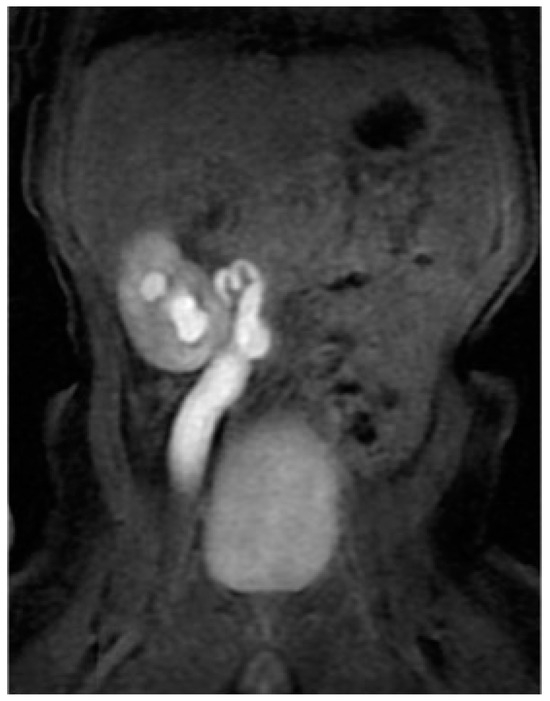

Unfortunately, it was impossible to rise up the JJ ureteral stent to the stenotic PUJ; therefore, a percutaneous nephrostomy was achieved and left in place for one and a half month. Two weeks later, to discern the renal function after the acute hydronephrotic compression and pelvic rupture, he underwent dynamic scintigraphy that showed a symmetric renal function with a right obstructive pattern. To completely understand the anatomy of the right upper urinary tract, a magnetic resonance imaging (MRI) was performed, showing a dysplastic appearance of the PUJ with a coiled junctal ureter and a distal ureter dilatation until the uretero-vesical junction (UVJ) (Figure 3).

Figure 3.

Hydronephrosis on a corkscrew pyeloureteral junction with primary obstructive megaureter at the magnetic resonance imaging.